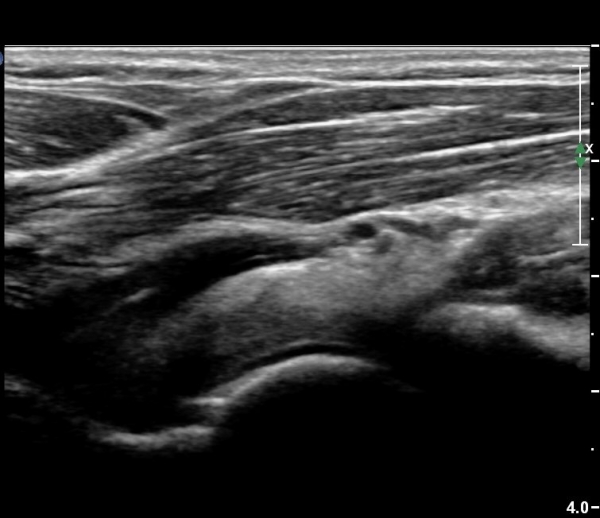

¿Ü»ó°ú¿Í ½ÅÀü°Ç Á¾´Ü¸é°Ë»ç¿¡¼­ ƯÀÌ ¼Ò°ß º¸ÀÌÁö ¾ÊÀ½(»çÁø 1)

³»»ó°ú¿Í ±¼°î°Ç Á¾´Ü¸é°Ë»ç¿¡¼­ ƯÀÌ ¼Ò°ß º¸ÀÌÁö ¾ÊÀ½(»çÁø2).

¼ÒµÎ Á¾´Ü¸é°Ë»ç¿¡¼­ ¼ÒµÎ¿Í ¿ä°ñµÎ Àü¹æ¿¡ ¼ö¾×Àú·ù°¡ °üÂûµÊ(»çÁø 3, 4).

ÁÖµÎ¿Í Á¾´Ü¸é°Ë»ç¿Í Ⱦ´Ü¸é°Ë»ç¿¡¼­ ÁֵοͿ¡ ÀÌÁúÀû¿¡ÄÚ¸¦ º¸ÀÌ´Â

´Ù·®ÀÇ ¼ö¾×Àú·ù°¡ °üÂûµÊ(»çÁø 5, 6).